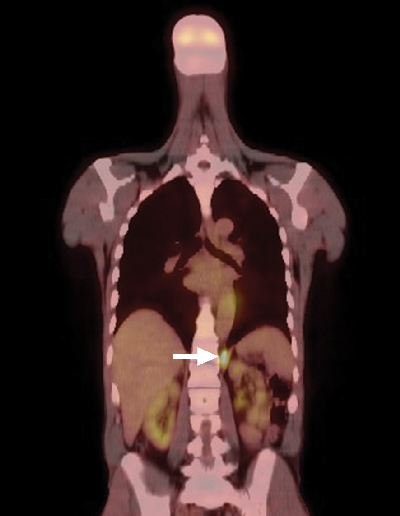

A positron emission tomography scan showed mildly increased fludeoxyglucose activity at the right thyroid bed, consistent with low-volume residual disease, and intense activity in the left retrocrural soft tissue (Box 2). Biopsy specimens were obtained from both sites and were found to be histologically consistent with parathyroid cancer. The patient underwent a planned resection of the known sites of disease, beginning with a right-sided neck dissection. Thereafter, he underwent a left thoracotomy, which showed more extensive pleural deposits and bulky metastatic disease over the diaphragm and crura, only amenable to debulking. A left pleural effusion, non-malignant on cytology, complicated his postoperative recovery.